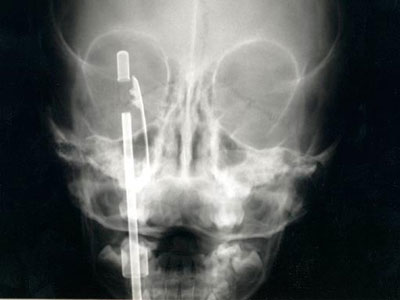

1. Người không may mắn này đã bị phần đầu của chiếc tuốc-nơ-vít đâm thẳng vào sau đầu. Tin hay không tin là tùy bạn nhưng các bác sĩ đã lấy được vật này ra và bệnh nhân đã phục hồi hoàn toàn: